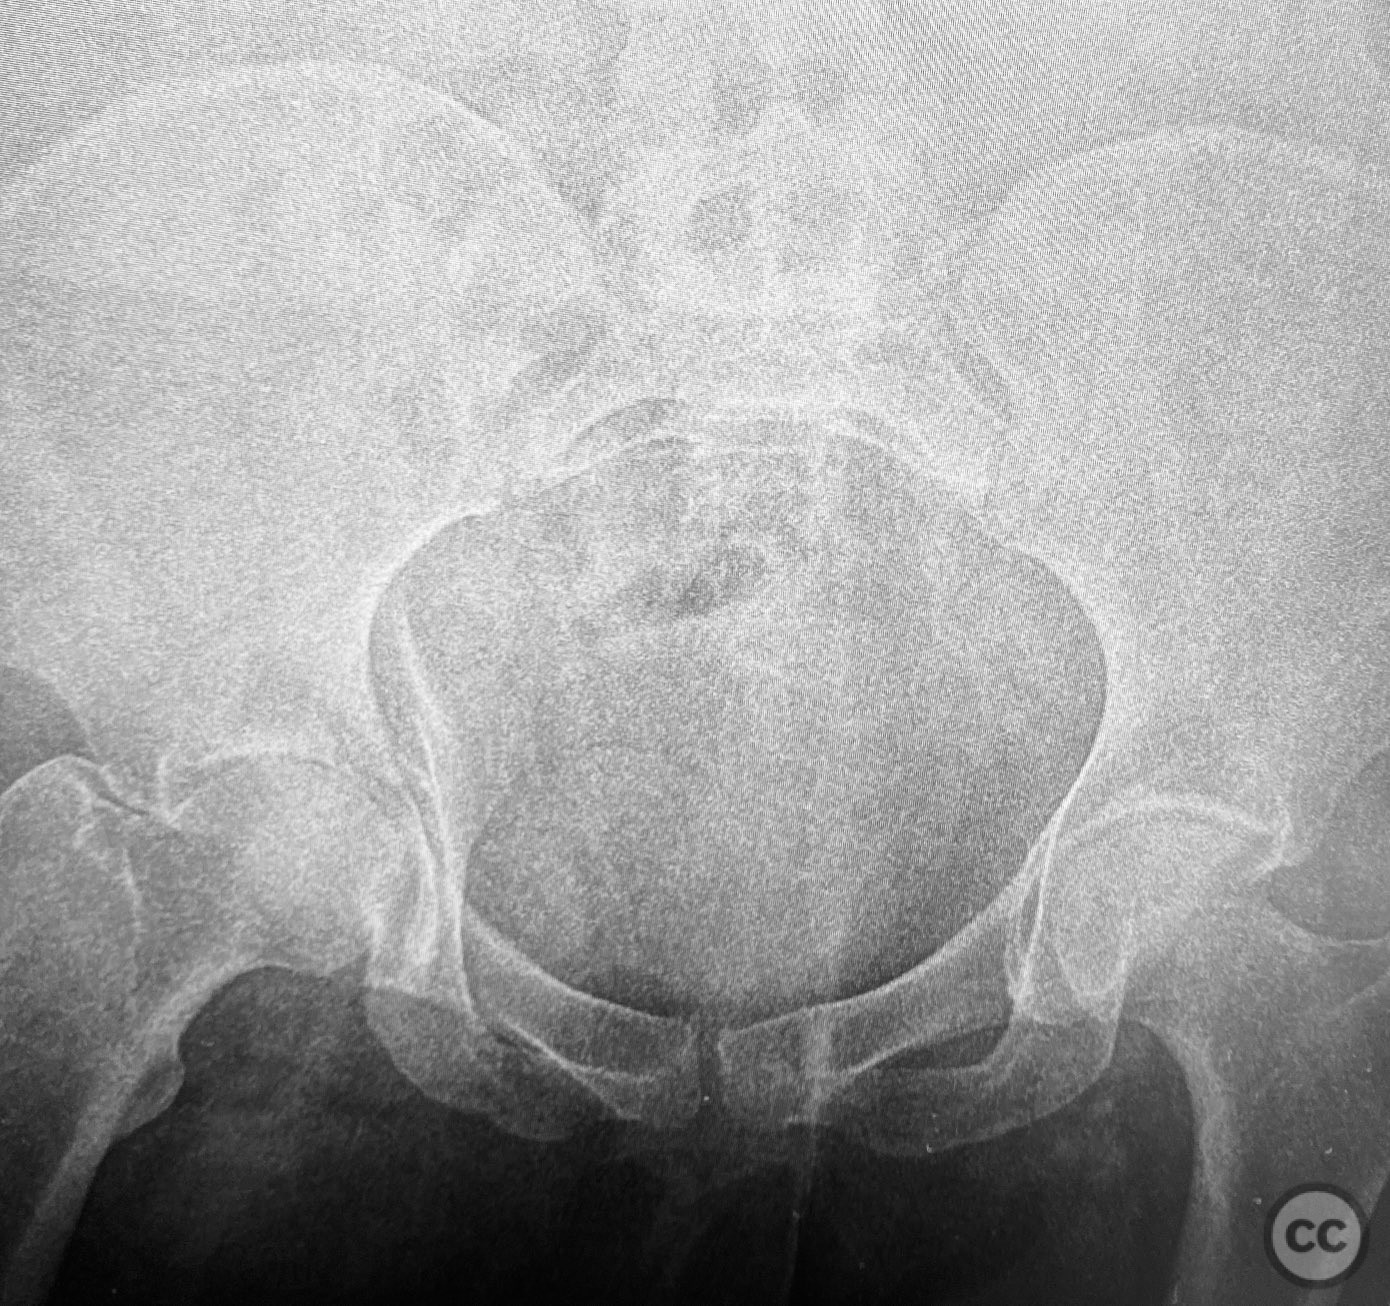

Clinical and radiological findings:  The patient is morbidly obese and sustained an unstable, displaced posterior column/posterior wall (PC/PW) acetabular fracture. Axial computed tomography images revealed a 2x2x1.5 cm pyramidal chondrocancellous articular fragment wedged in the fracture plane near the incisura ischiadica major (greater sciatic notch). Surface-rendered reconstructions further delineated the fracture morphology and fragment position. Obesity was noted to complicate all aspects of management, including anatomical localization, intraoperative imaging, and soft tissue handling.